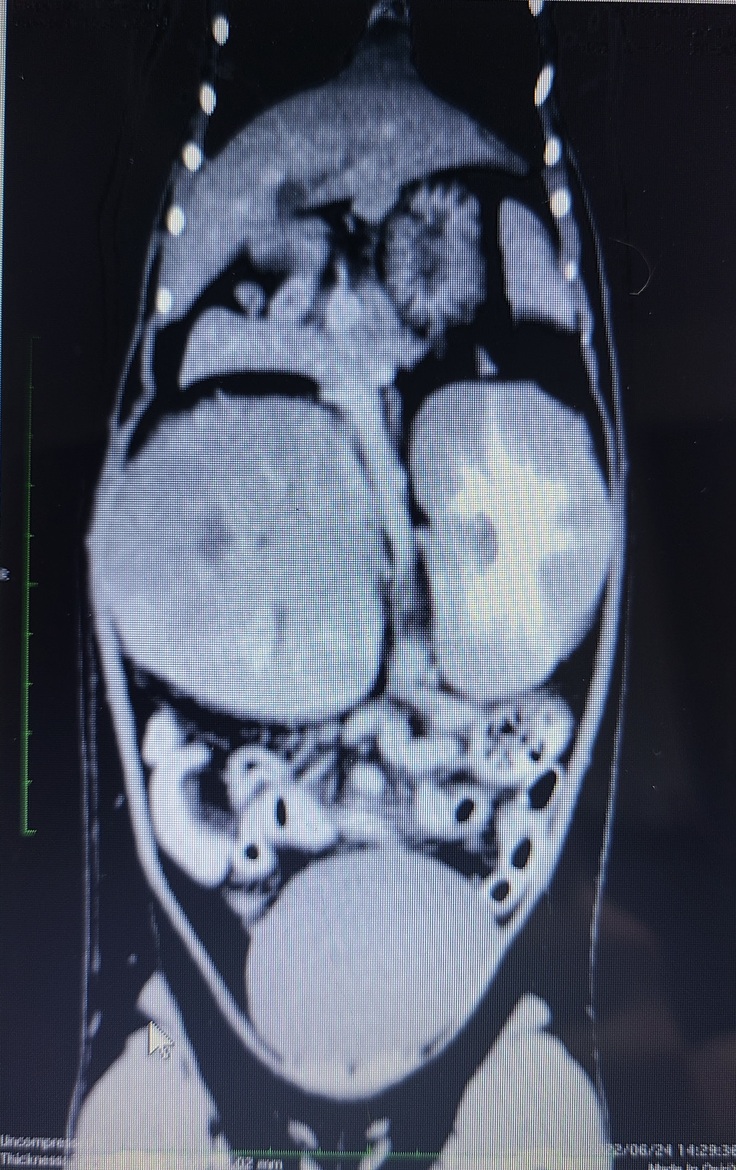

疾患名:縦隔型悪性リンパ腫、腎臓リンパ腫

6/22の夜、ルルの呼吸がいつもより速く、苦しいのか時々大きく息をしていることに気づき夜間救急病院受診しました。胸水(リンパ液)が溜まっているとのことで肺が圧迫され呼吸困難となっていたようで、酸素濃度の高い部屋に入院することとなりました。数日にわたりレントゲンやCT、エコー、採血などの検査をしてもらった結果、縦隔型悪性リンパ腫、腎臓リンパ腫と診断されました。その日は、飼い主としてもっと早くルルの病気に気づいてあげられたらルルは苦しい思いをせずに済んだと思い涙が止まりませんでした。

▲腫瘍により胸水貯留と腎臓が大きく肥大している写真

獣医師さんには1日で100mlほどの胸水が溜まっている状態で、定期的に針を刺して水を抜いても数ヶ月の命で、助かるためには早急に抗がん剤治療を行う必要があると宣告されました。幸い白血病ウイルスが原因のリンパ腫ではないことから、抗がん剤の効き目がよく長期生存する猫もいると獣医師さんに教えてもらいました。「助かる可能性があるのに治療せずこのままルルを死なせるわけにはいかない」、「ルルの家族としてルルを幸せにするんだ」という思いから、ルルのがんが完治することを信じて抗がん剤治療を行うことを決意しました。